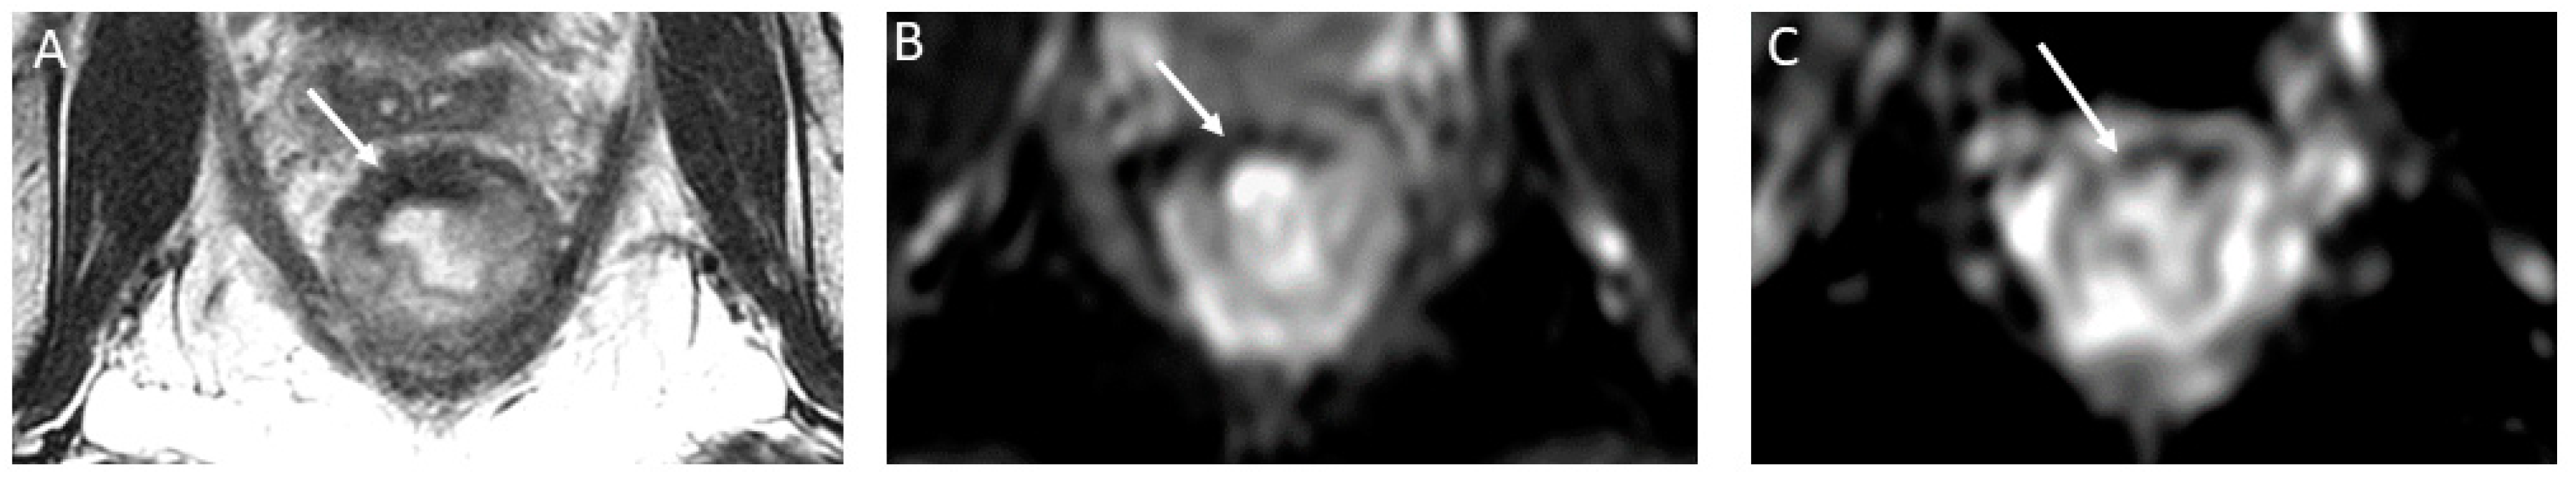

Figure 6.

T2 shine-through effect mimicking residual tumor in a 58-year-old man with rectal adenocarcinoma. Axial T2-weighted MR image after the completion of neoadjuvant chemoradiotherapy shows a thick scar along the tumor bed (arrowhead), and mucin extension into the left mesorectal space is noted at the 2:00 to 4:00 position (arrow) (A). On the corresponding axial diffusion-weighted image, there is a notable high signal at the same location as the mucin extension (arrow) (B). An axial apparent diffusion coefficient map (ADC) further confirms the presence of high signal intensity at the location of the mucin extension (indicated by the arrow) (C). This high signal intensity observed on both the diffusion-weighted image and the ADC map indicates the T2 shine-through effect, signifying non-restricted diffusion.

On the other hand, “T2 dark-through” is when extensive post-treatment fibrosis results in a low signal on the ADC map. This phenomenon results in part from the high collagen content of fibrosis. To avoid this, the reader should correlate the low signal seen on the ADC map with the signal on DWI and T2-weighted imaging; if the signal is low on all sequences, then it should be interpreted as fibrosis (Figure 7) [73].